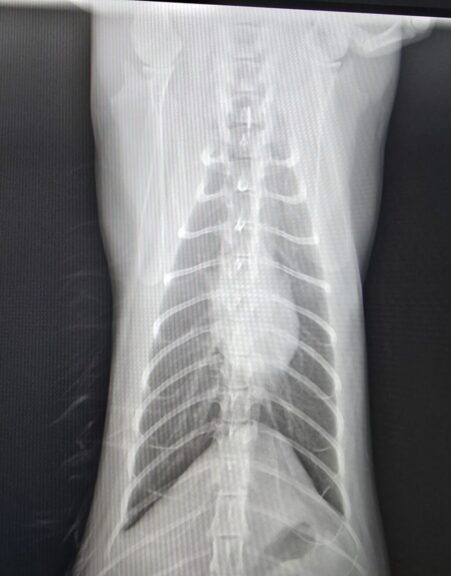

そこで念のためにって撮ってもらったレントゲン

白いモヤモヤが薄くなっているのお分かり頂けますか?

治ってきてるんです。

やっぱり治らない肺炎じゃなかった!これが治れば今度こそ今度こそやっと何も心配ない体で生きていけるんだっ!!!